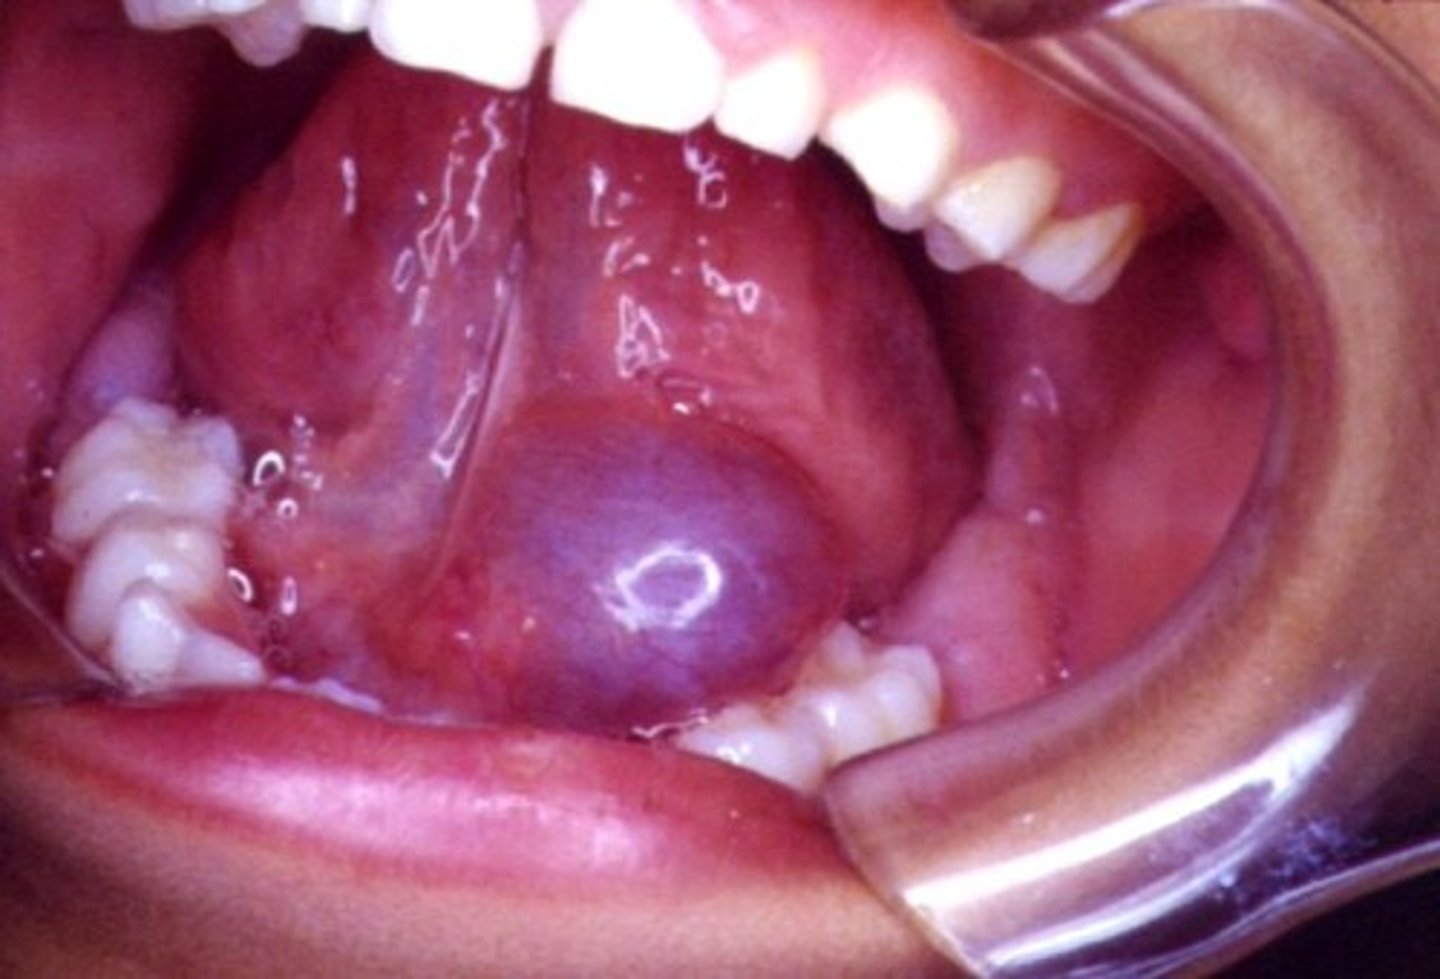

Name the pathology: oral manfestation in aids patients. a malginant cnacer of the lining of blood vesels on the ______. May present as purple lesionson the palte. TX: ?

kaposi sarcoma

hard palate

tx: provide normal dntal treatment but NO invasive treatment